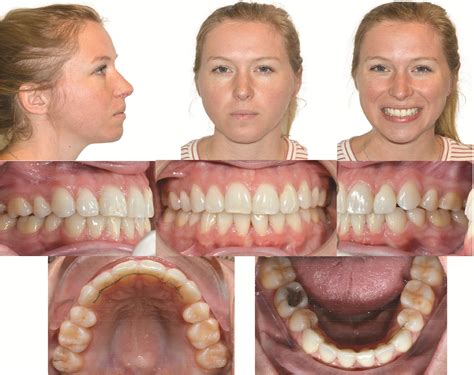

The progression of ICR can lead to significant changes in a person’s bite and facial profile. As the condyle shrinks, the lower jaw (mandible) shifts backward and upward, often resulting in an anterior open bite, where the front teeth no longer meet even when the back teeth are touching. This change can occur rapidly or slowly, often causing distress to patients who notice their smile or facial structure shifting unexpectedly.

Because the condition often mimics other TMJ disorders, diagnosis can be challenging. Patients typically seek help only when they notice visible changes in their appearance or discomfort in their jaw joint. Key symptoms to monitor include:

• Progressive open bite: A noticeable gap developing between top and bottom front teeth.

• Facial asymmetry: A receding chin or a chin that appears to be drifting to one side.